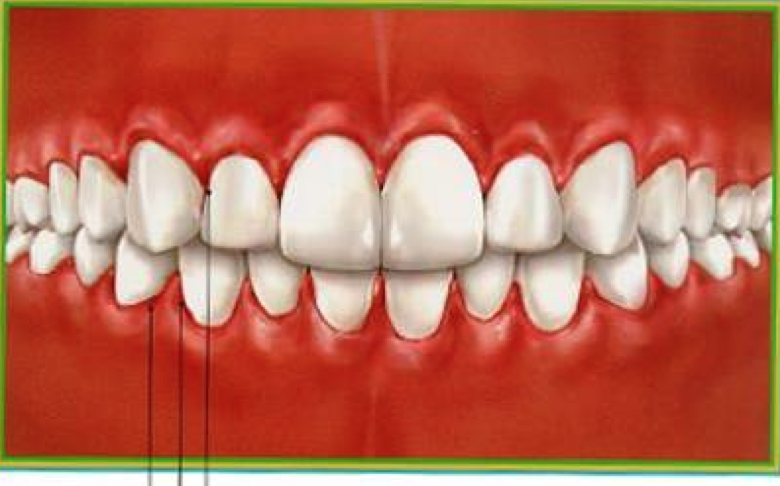

acute ulcerative gingivitis